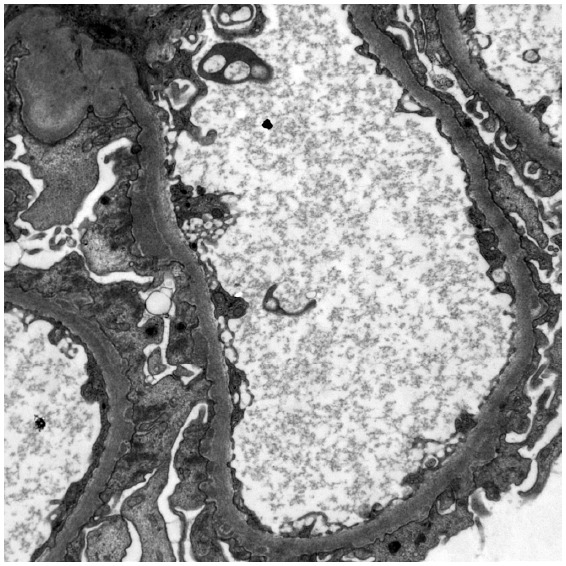

Membranous nephropathy (MN) is a rare autoimmune disease, in which the circulating autoantibodies against antigens attack podocytes. Neural Epidermal Growth Factor like 1 (NELL1) 1-associated MN is the second most common antigen, following phospholipase A2 receptor. Complementary and alternative medicine and malignancies play a pivotal role in the development of NELL1-MN. This retrospective study describes the clinical characteristics, therapeutic strategies, and longitudinal outcomes in patients with NELL1-MN at our center.

Abstract Image